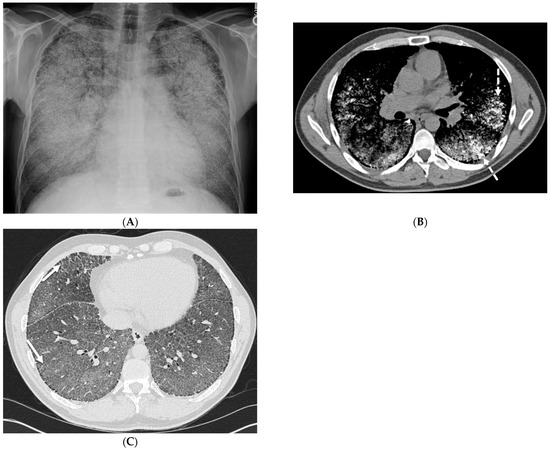

2.1. COVID-19 Pneumonia

2.2. Bacterial Pneumonia

4.7. Pulmonary Vein Stenosis (PVS)